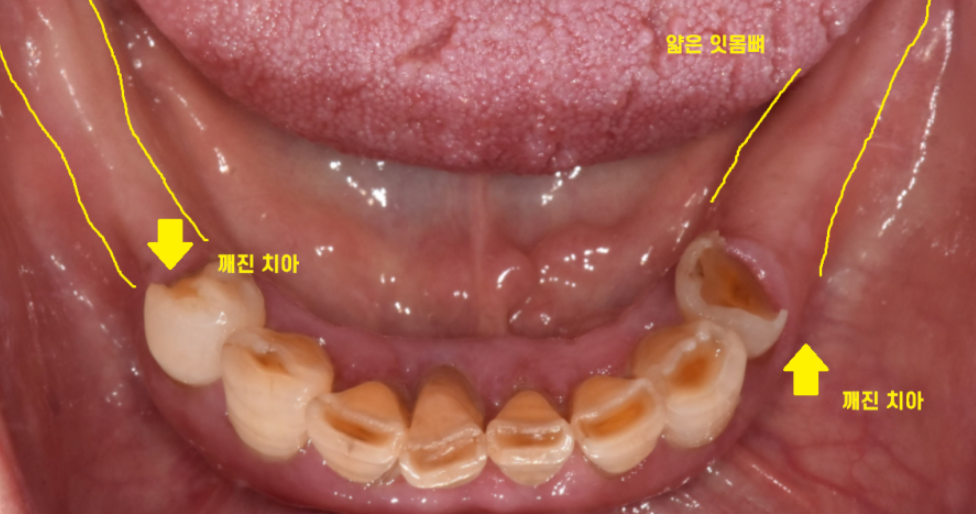

아래 치아의 경우 깨지고

치아가 뽑힌지 오래되어 잇몸뼈가 얼마 없는 상황이었습니다.

발치 후 치아의 모습이죠~?